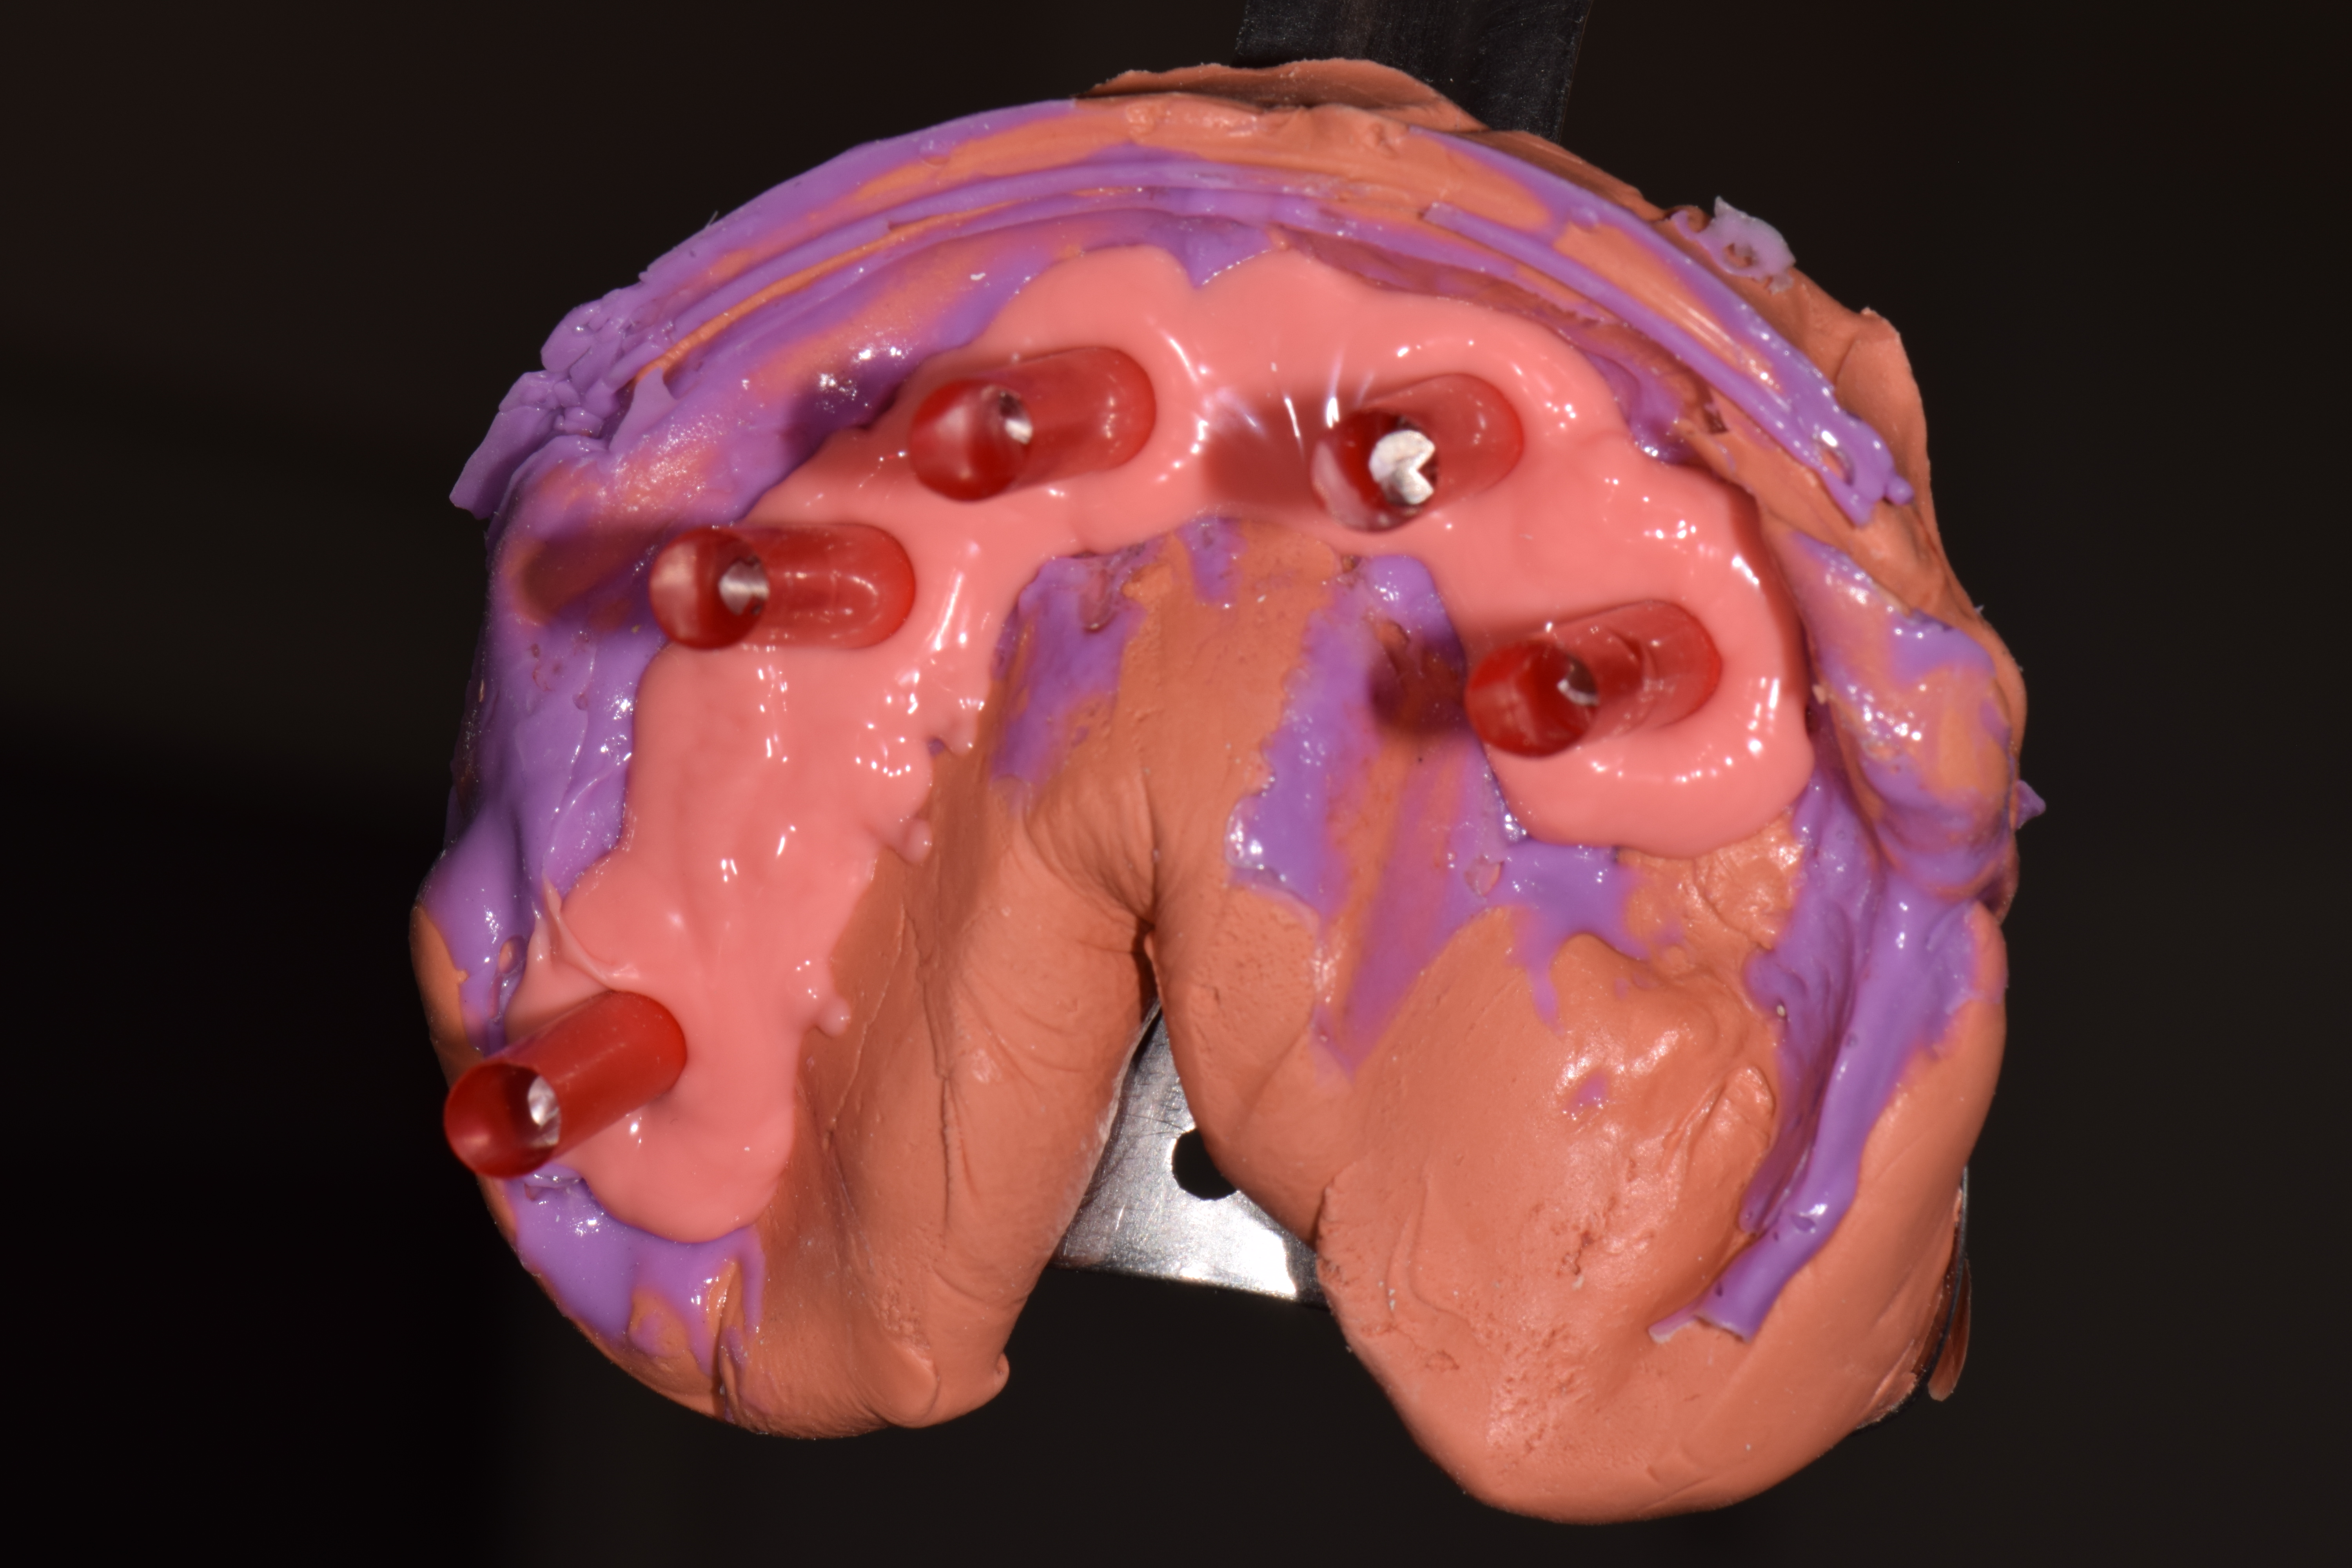

| ИМПЛАНТАЦИЯ |

|

|

|

|

|

|